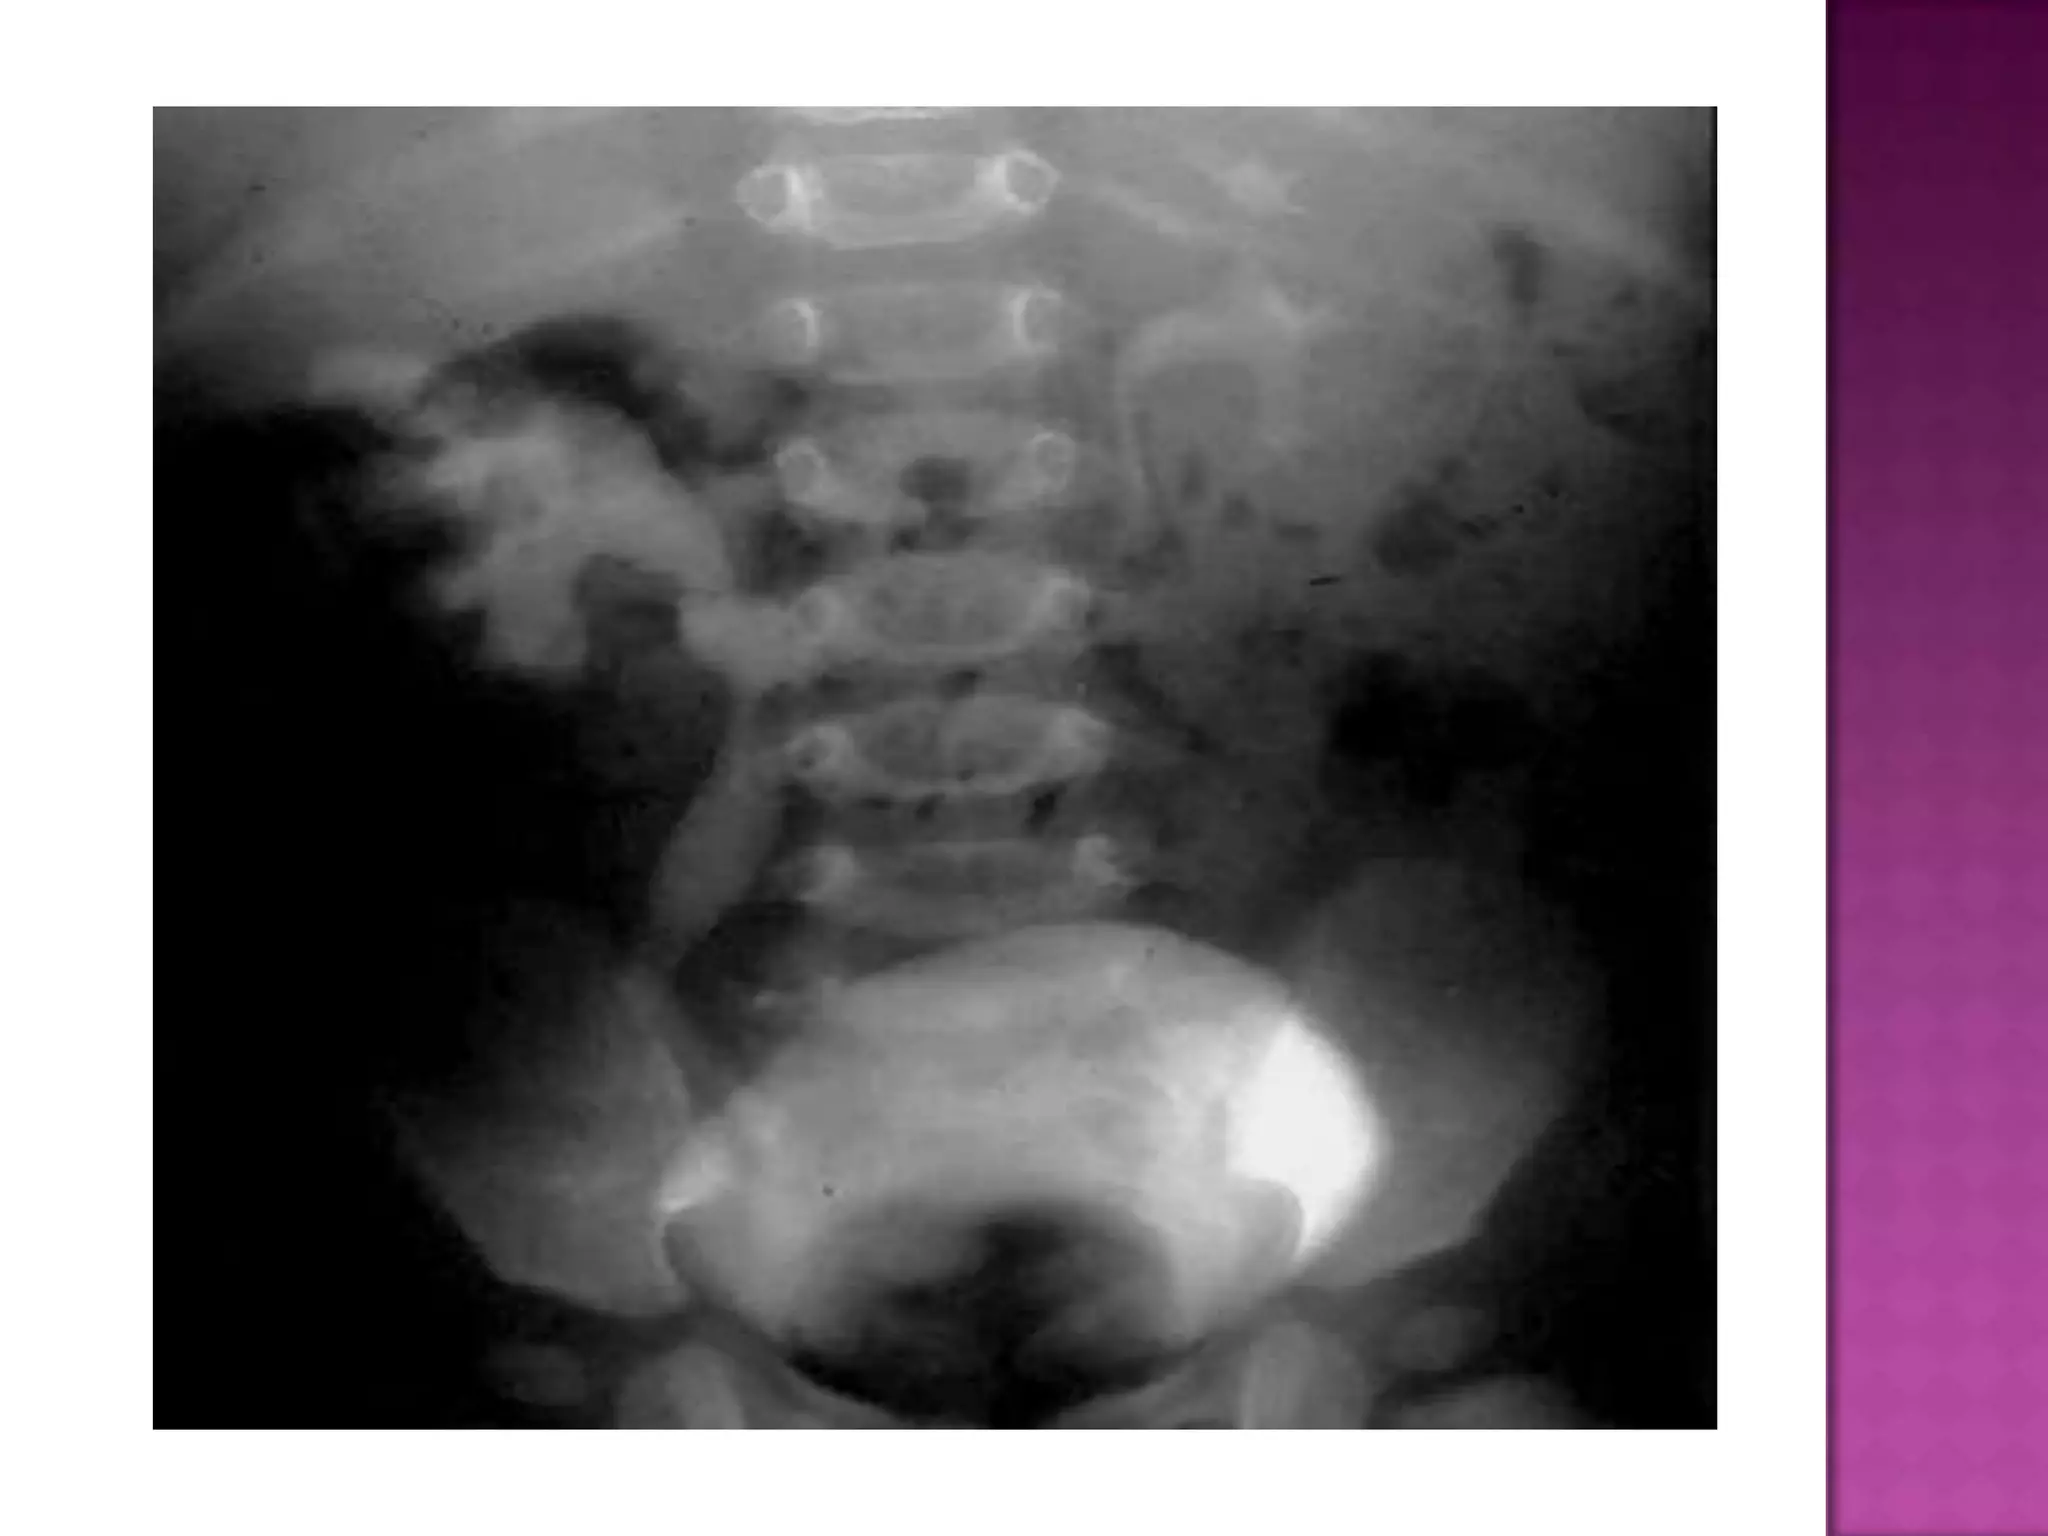

Post Micturition film to demonstrate the bladder emptying success, and the

return of the previously distended lower ends of ureters to normal.

Post Micturition filmto demonstrate the bladder emptying success, and the return of the previously distended lower ends of ureters to normal.